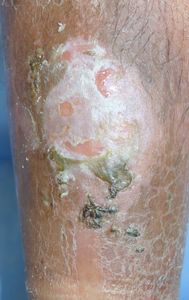

51歳男。

2016年3月下旬,自転車に乗っていて転倒し,右下腿外側を擦りむいた。4日後,〇〇病院整形外科を受診,骨折はないと言われ,ゲンタシン軟膏を処方され,通院は必要ないと説明された。様子を見ていたが治らないため,4月中旬に自宅近くの△△内科医院を受診し,ゲンタシン軟膏が処方された。5月連休明けに再受診したところ,「外科の病院で手術が必要」と説明された。その説明に不信感をいだき,ネットで検索。

5月18日,当科受診。創面に付着している痂皮を除去してプラスモイストで被覆。2日で完治。

5月18日 痂皮除去後 5月20日